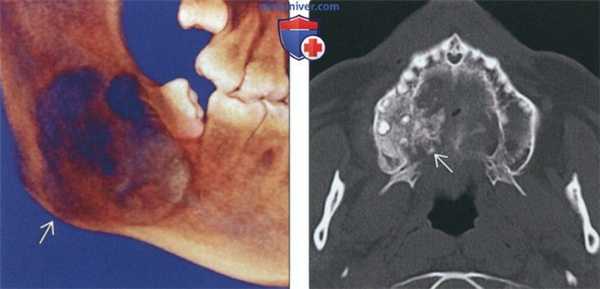

(Слева) Трехмерная реконструкция (вид со стороны язычной поверхности) у этого же пациента позволяет оценить выраженность распространения в нижнюю кортикальную пластинку и дольчатый характер образования.

(Справа) На аксиальной КТ без КУ в верхней челюсти определяется хондросаркома низкой степени злокачественности в виде рентгеноконтрастною образования альвеолярного отростка нижней челюсти справа, имеющего неправильные, грубые края, типичные для злокачественной опухоли. В структуре образования присутствуют точечные обызвествления.